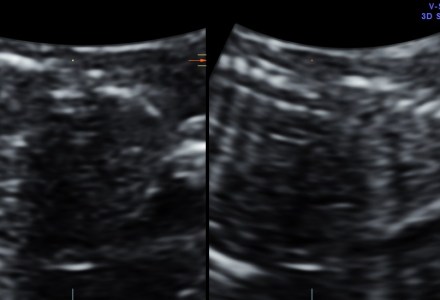

NEURAL TUBE DEFECT